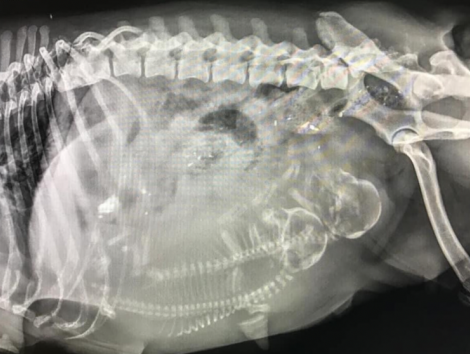

RADIOLOGIA